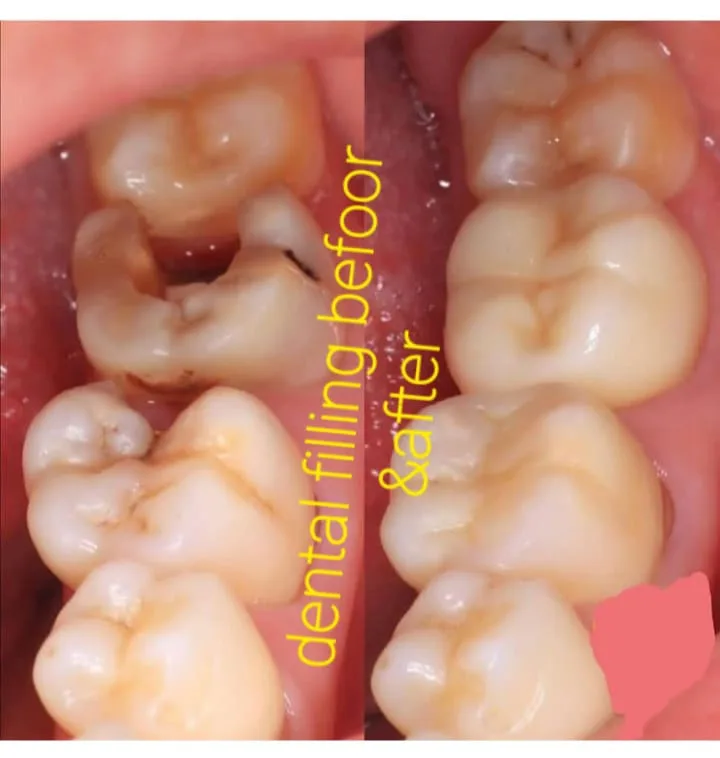

✅ Behandlung von Zähnen und Zahnfleisch jeglicher Komplexität